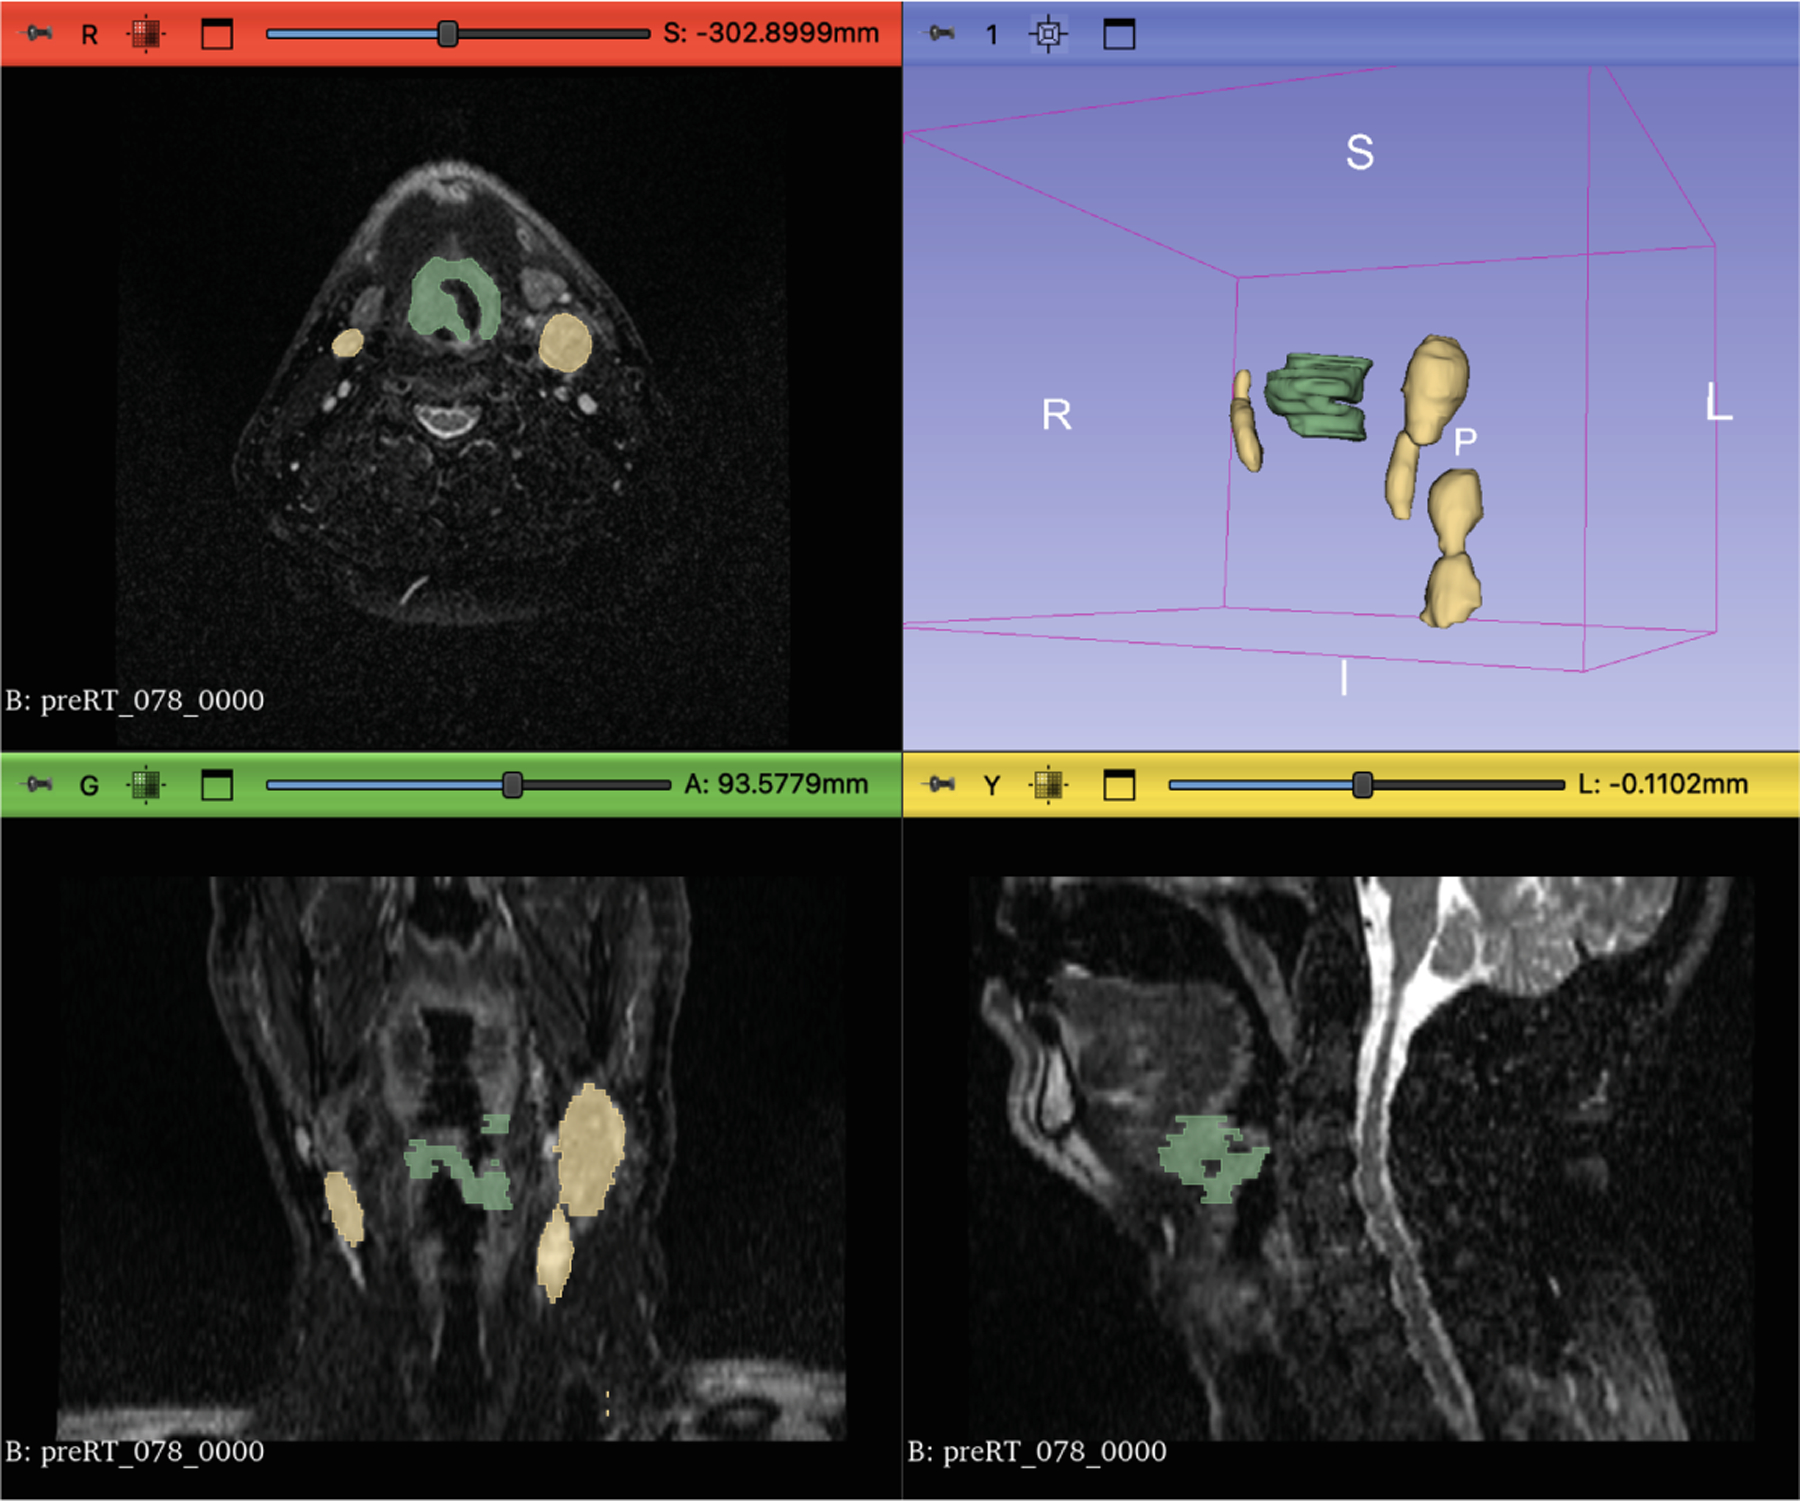

Radiation therapy (RT) is essential in treating head and neck cancer (HNC), with magnetic resonance imaging (MRI)-guided RT offering superior soft tissue contrast and functional imaging. However, manual tumor segmentation is time-consuming and complex, and therefore remains a challenge. In this study, we present our solution as team TUMOR to the HNTS-MRG24 MICCAI Challenge which is focused on automated segmentation of primary gross tumor volumes (GTVp) and metastatic lymph node gross tumor volume (GTVn) in pre-RT and mid-RT MRI images. We utilized the HNTS-MRG2024 dataset, which consists of 150 MRI scans from patients diagnosed with HNC, including original and registered pre-RT and mid-RT T2-weighted images with corresponding segmentation masks for GTVp and GTVn. We employed two state-of-the-art models in deep learning, nnUNet and MedNeXt. For Task 1, we pretrained models on pre-RT registered and mid-RT images, followed by fine-tuning on original pre-RT images. For Task 2, we combined registered pre-RT images, registered pre-RT segmentation masks, and mid-RT data as a multi-channel input for training. Our solution for Task 1 achieved 1st place in the final test phase with an aggregated Dice Similarity Coefficient of 0.8254, and our solution for Task 2 ranked 8th with a score of 0.7005. The proposed solution is publicly available at Github Repository.